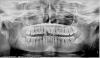

Nata719 Опубликовано 27 января, 2013 Поделиться Опубликовано 27 января, 2013 Здравствуйте.Помогите,пожалуйста,определиться со способом протезирования.Пару лет назад вдруг стали кровоточить десны и буквально за короткий промежуток времени изменили свое положение два верхних центральных зуба: один выдвинулся вперед, а другой “ушел” назад. А между левым зубом и соседним образовалась щель примерно в 4 мм. (небольшая была и раньше). Сделала панорамный снимок и пошла к врачу. Врач,посмотрев снимок, сказала, что с правой стороны уменьшение костной ткани, глубокий прикус, а двум верхним зубам помогут коронки. За два посещения мне сняли зубной и поддесневой камень и приступили к протезированию. Поставили две отдельно стоящие безметалловые коронки с вкладками. Щель между правым верхним и соседним зубом осталась, так как врач сказала, что она достаточно большая и ее не убрать. Вид,конечно был не очень, но хотя бы два верхних зуба стали ровными.Через полтора года ситуация практически повторилась. Десны начали кровоточить, правая коронка чуть выдвинулась вперед, соседняя наклонилась вбок градусов на 10 (боюсь, как бы не вылетела), да еще заметила, что последние зубы справа на верхней и нижней челюстях стали пошатываться.Была на консультации у трех врачей. Двое сказали, что можно поставить мост из 6-ти единиц, выровняв и закрепив зубы. Третий вынес приговор: мост ставить нельзя, только "косметическую" пластинку из акрила, так как пародонтит не лечится, зубы я все равно потеряю. Конец один - беззубая челюсть и протез. Из снимков затребовал только прицельные снимки 3,2,2,3 зубов.Неужели все так печально и мне надо будет привыкать с съемному протезу (не представляю, как это)? Спасибо. Ссылка на комментарий

Kotyara Опубликовано 27 января, 2013 Поделиться Опубликовано 27 января, 2013 Не хочется вас расстраивать, но с 5 по 5 на верх челюсти включительно надо удалять.И ставить имплантаты. Не тратьте свое время и деньги на бессмысленное лечение пародонтита.Внизу тоже интересно. Ссылка на комментарий